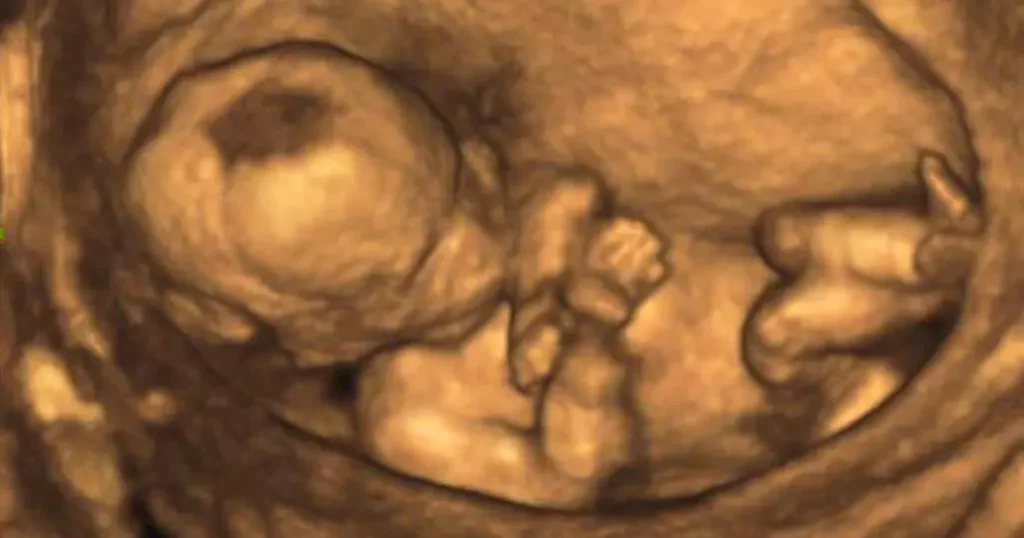

Während des Screenings wird der Arzt mithilfe eines Ultraschallgeräts Bilder des ungeborenen Kindes auf einem Bildschirm erzeugen. Der Arzt wird die Bilder sorgfältig betrachten und die verschiedenen Organe des Kindes auf ihre korrekte Entwicklung und Größe untersuchen.

Mit Hilfe des Ultraschalls werden verschiedene Organe des Fetus untersucht, um sicherzustellen, dass sie sich korrekt entwickeln und keine Auffälligkeiten aufweisen. Zu den untersuchten Organen gehören:

- Gehirn: Kleinhirn und Seitenventrikel

- Magen

- Harnblase

- Vordere Bauchwand

- Haut am Rücken

- Herz (orientierend)